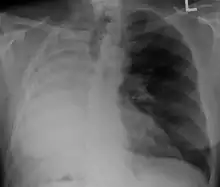

Pleural effusion

.jpg)

A pleural effusion is an accumulation of fluid inside the pleural space. If this collection of fluid gets large enough, it can also push structures in the chest away from it and cause a mediastinal shift. However, a pleural effusion can also pull the mediastinal structure towards itself. If this is the case, then there is an underlying condition causing the collapse of the lung on that side. An example is a tumor obstructing a bronchus and causing lung collapse and pleural effusion.[3]